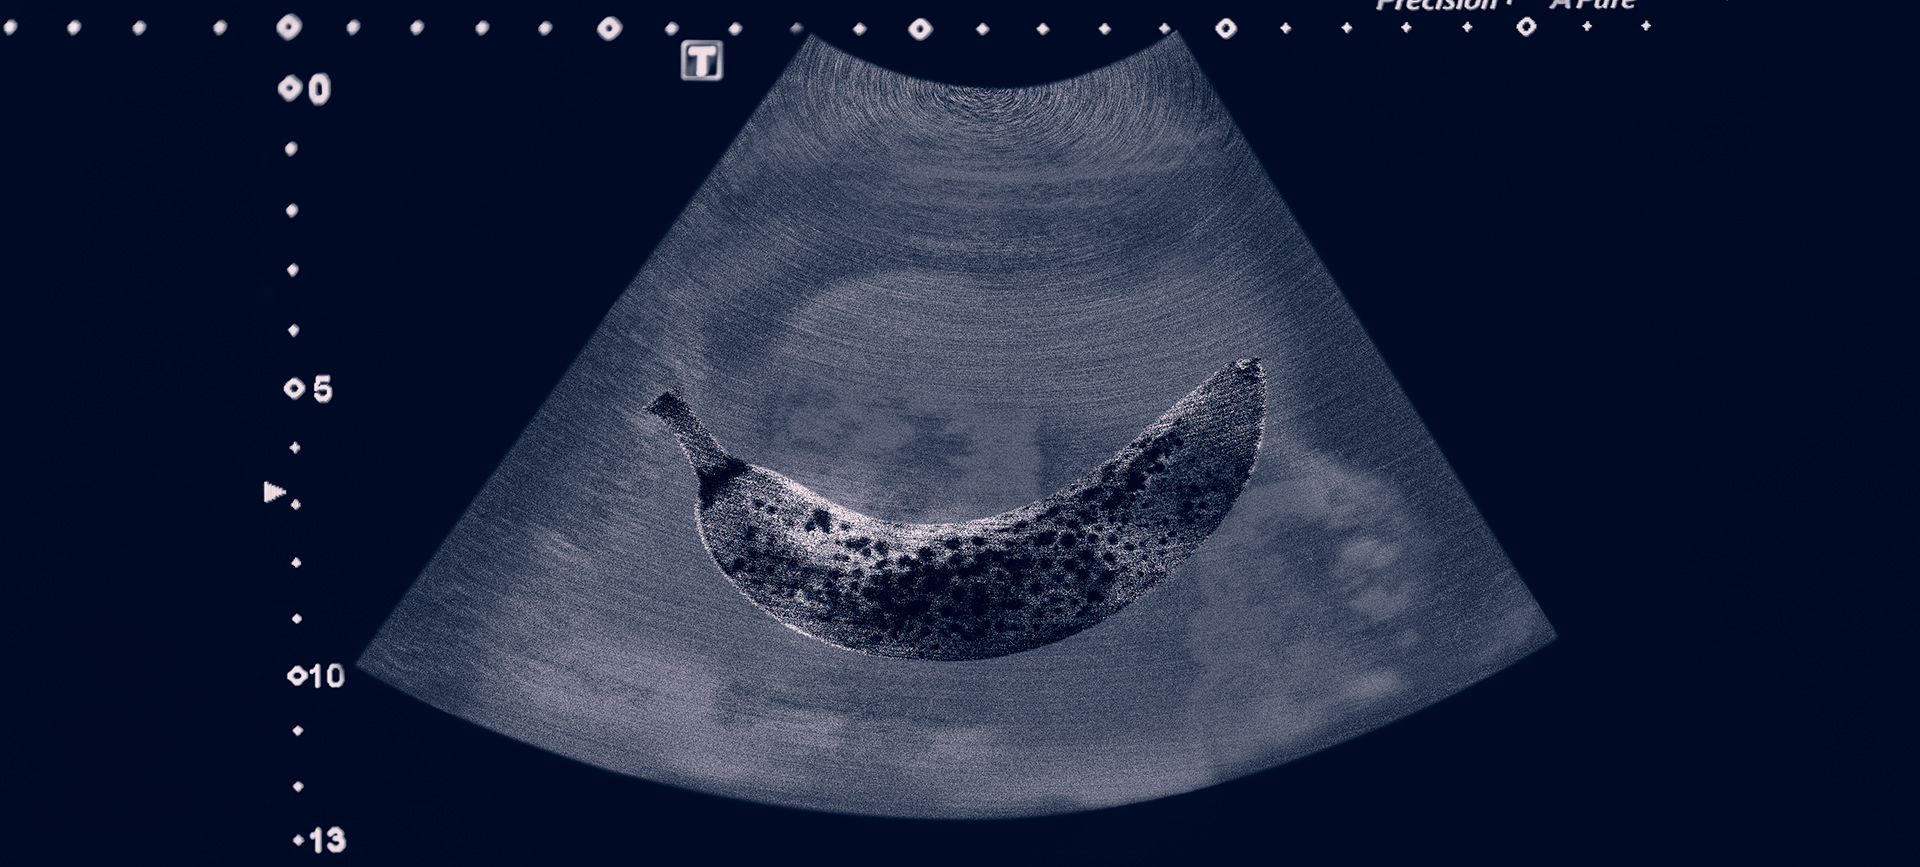

The penile ultrasound is similar to most common ultrasounds, said Cohen, an assistant professor of urology and director of sexual medicine at NYU Langone Health. Ultrasounds are good tools to use on the penis because they don't use radiation or transmit much heat, which is why they can be used on the belly of a pregnant woman.

A PDDU involves placing an ultrasound probe along the side of the penis. Different crystals within the probe measure frequencies within the body.

"It's picking up different signal frequencies, whether thicker like muscle or thinner like fat, and then it reads it out on the display machine," Cohen said.